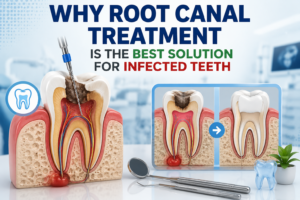

Robotic and Minimally Invasive Surgical Methods

Surgical oncology has benefited significantly from robotic-assisted and minimally invasive techniques. These approaches allow surgeons to operate with enhanced visual clarity and controlled movement. Smaller incisions result in reduced blood loss and shorter hospital stays. Robotic systems support complex procedures in which precision directly affects recovery and function. Faster healing also enables patients to proceed with chemotherapy or radiation without unnecessary delays. Surgical innovation continues to play a key role in improving outcomes within cancer treatment in Mumbai.